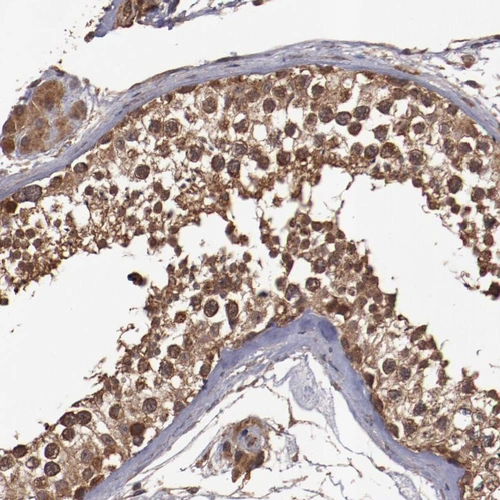

Immunohistochemical staining of human testis shows strong cytoplasmic positivity in cells in seminiferous ducts.